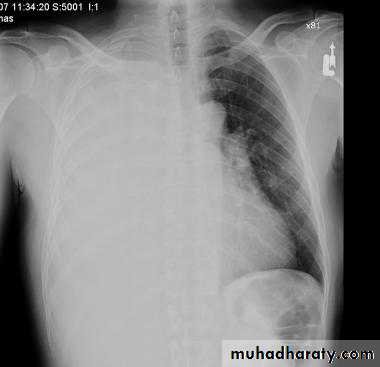

X-ray hemothorax

X-ray pneumohemothorax